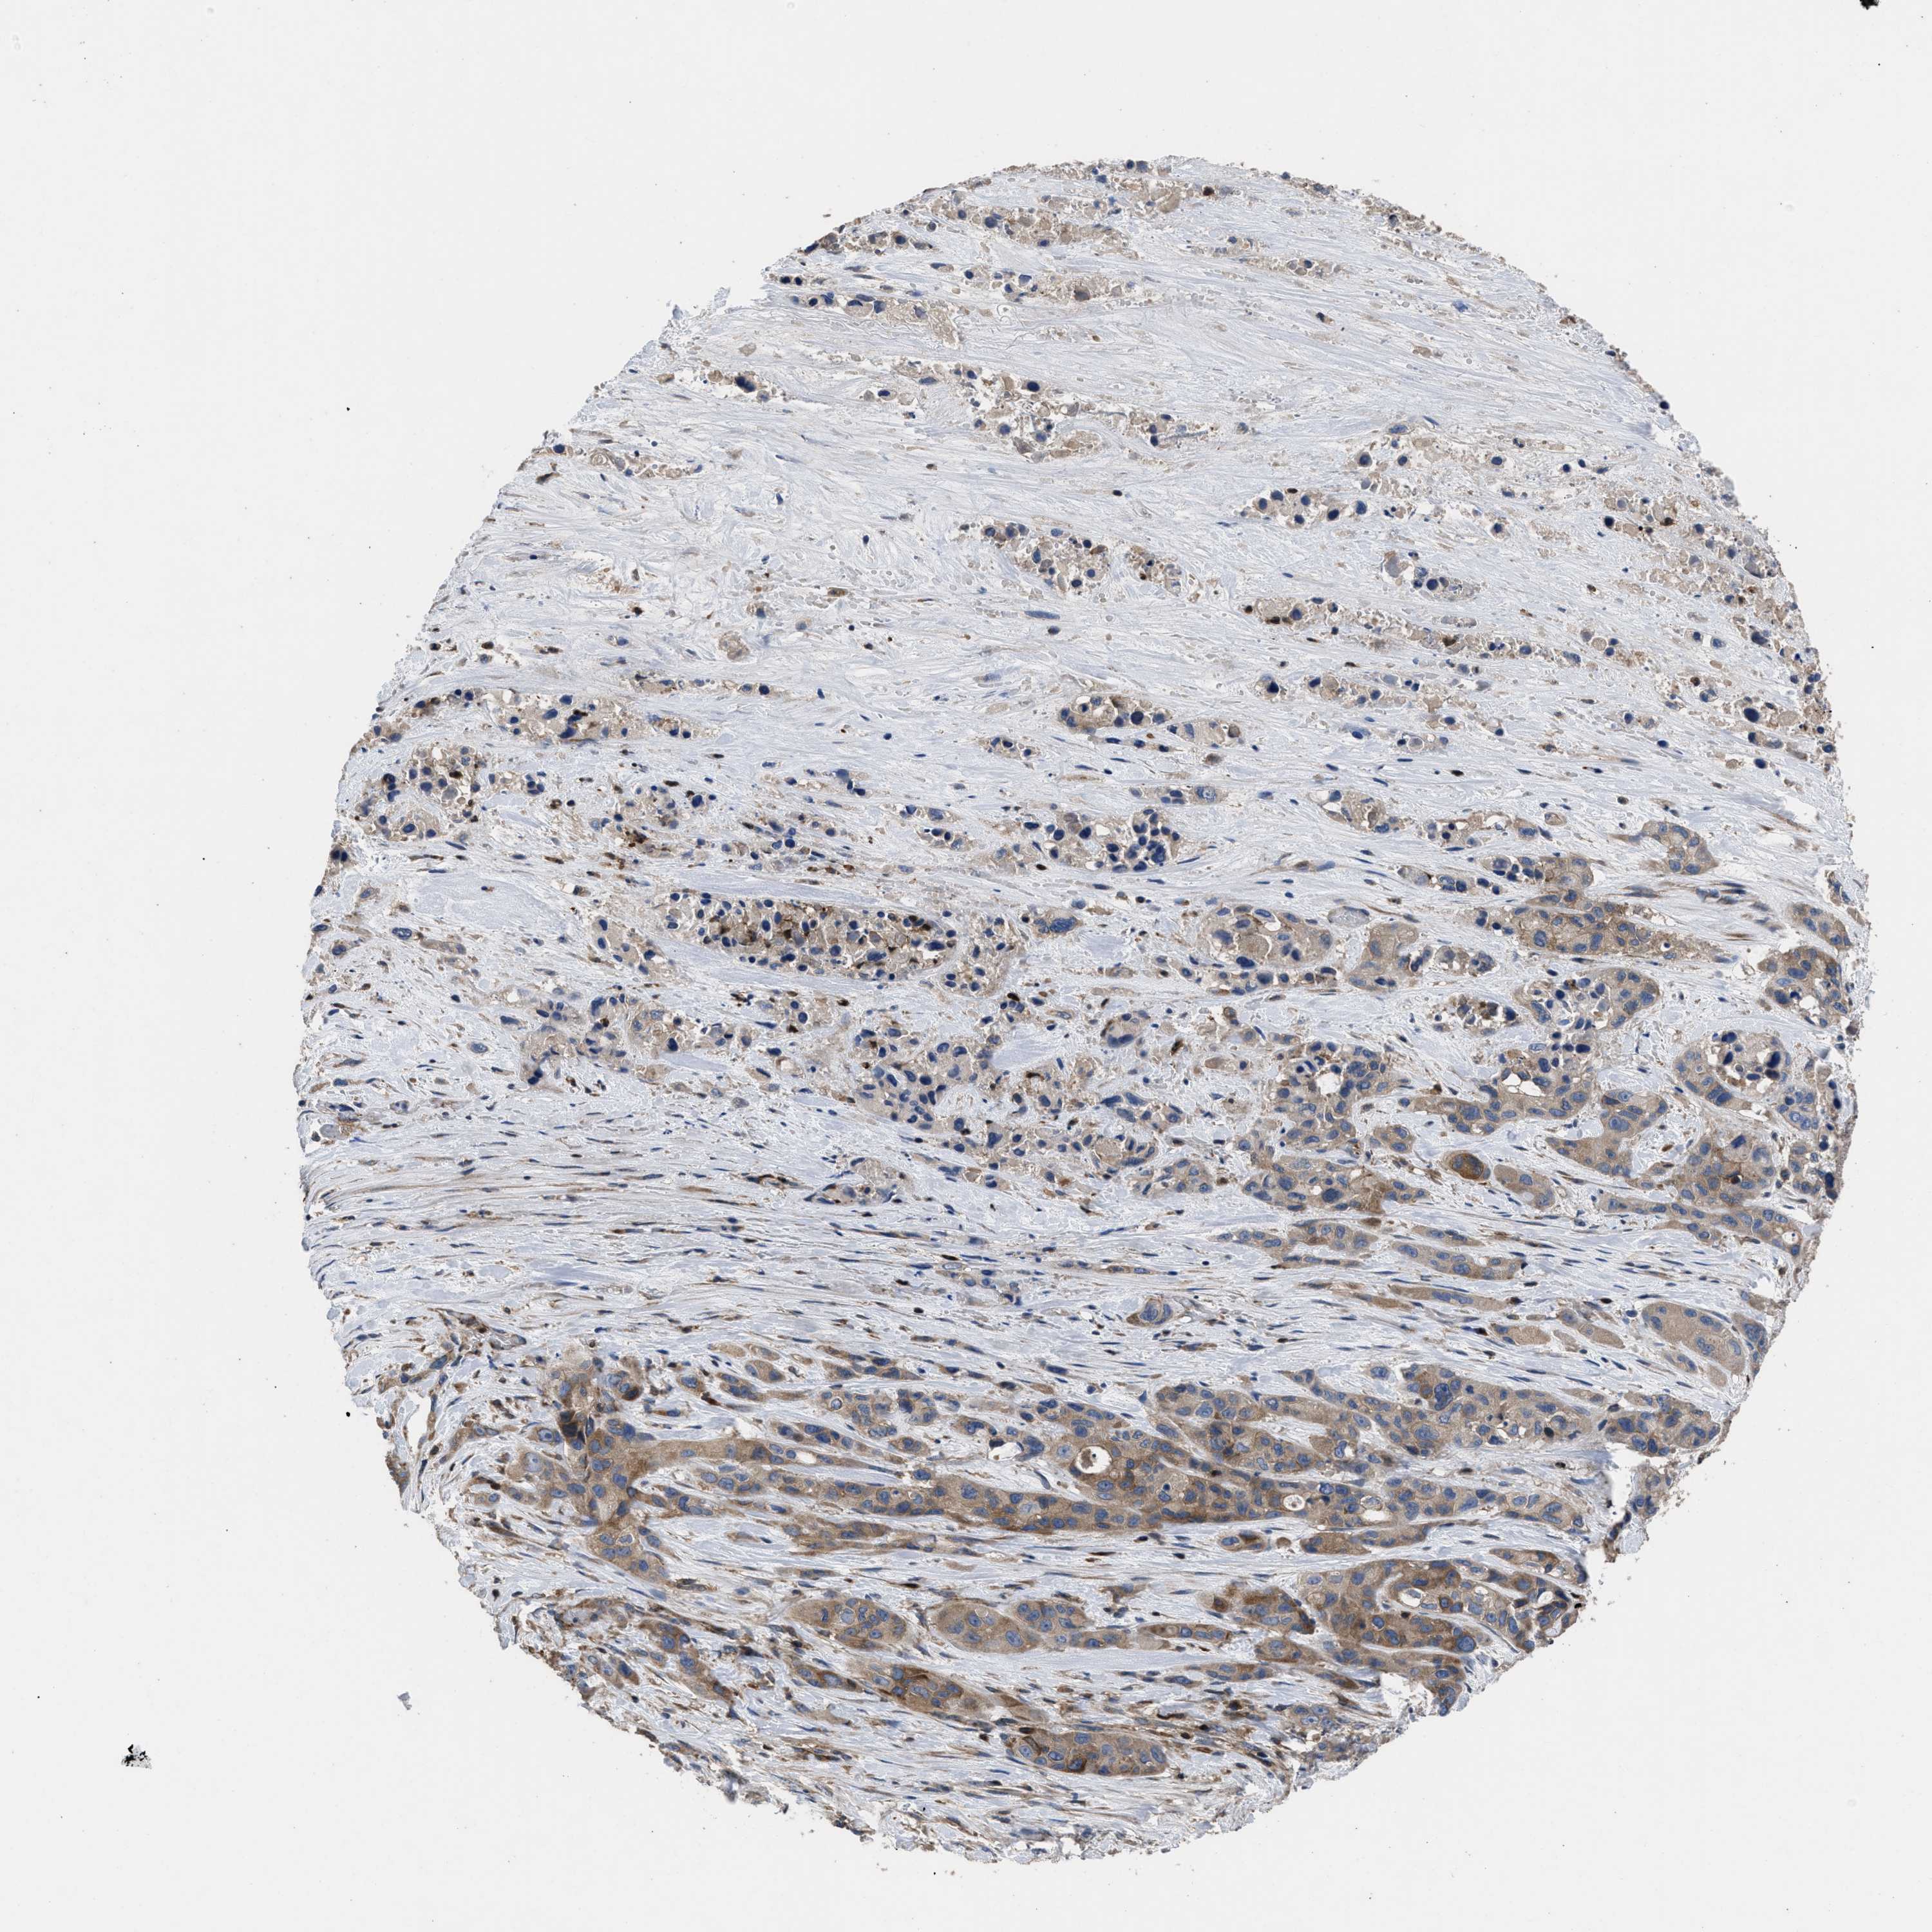

PANCREATIC CANCER - Protein expressioni

A mouse-over function shows sample information and annotation data. Click on an image to view it in a full screen mode. Samples can be filtered based on level of antibody staining by selecting one or several of the following categories: high, medium, low and not detected. The assay and annotation is described here.

Note that samples used for immunohistochemistry by the Human Protein Atlas do not correspond to samples in the TCGA dataset.

Antibody stainingi

Antibody staining in the annotated cell types in the current human tissue is reported as not detected, low, medium, or high, based on conventional immunohistochemistry profiling in selected tissues. This score is based on the combination of the staining intensity and fraction of stained cells.

Each image is clickable and will lead to virtual microscopy that enables deeper exploration of all samples and also displays staining intensity scores, fraction scores and subcellular localization as well as patient and tissue information for each sample.

Antibody HPA018162

Staining

High

Medium

Low

Not detected

Intensity

Strong

Moderate

Weak

Negative

Quantity

>75%

75%-25%

<25%

None

Location

Nuclear

Cytoplasmic/membranous

Cytoplasmic/membranous,nuclear

Adenocarcinoma, NOS